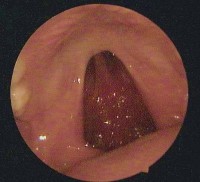

Hình ảnh nội soi tai

Ảnh 6 MN có mức dịch MSBA. 1811255336 |